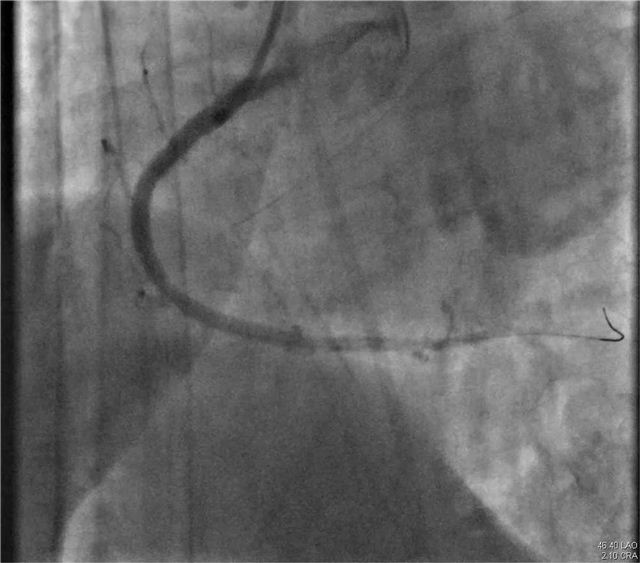

一面锦旗,不仅仅代表患者对疾病治疗效果的认可,更是对医护团队的认可。近日,年过八旬的逯奶奶和其家属将一面写有“精湛医术出妙手 体贴入微胜亲人”的锦旗送入长治市第二人民医院心血管内科医护人员手中,表达了患者对心血内科全体医护人员的感激之情。 患者家属说:“我母亲经过冯翠萍主任、王涛医生以及全体护理人员的积极治疗、精心护理,病情逐渐好转并康复出院。他们严谨、细心、热情的工作精神,精湛的医学技术,让我和我的家人非常感动和十分敬佩,非常感谢心血管内科全体医护人员,千言万语难表内心真情,唯有送上锦旗表示感谢。” 医术精湛 精心 患者逯奶奶已年过八旬,2023年11月发病至今的半年多时间里,多次因心肌梗死、心力衰竭,也多次就诊于我市多家医院;今年5月患者再次出现心绞痛症状,发作频繁,无法耐受,逯奶奶为求诊治就诊我院心血管内科进一步治疗。 入院后,主管医师王涛仔细询问病史并为其进一步进行检查。患者逯奶奶由于年岁已高,基础性疾病较多,既往曾在外院行冠脉造影术,血管扭曲,风险大。心血管内科主任冯翠萍、主管医师王涛再次为患者评估,患者为高龄,冠脉入路血管扭曲严重,手术风险极高;重新评估冠脉手术操作入路,因右桡动脉入路无法到达右冠,股动脉闭塞、狭窄无法进行穿刺,最终选择从左桡动脉进行手术。术中逯奶奶左侧动脉扭曲严重,在孙涛教授指导下,顺利找到罪犯血管,狭窄最重处达到99%,给予支架治疗,术后在心血内科医护人员的精心治疗和护理下,逯奶奶未再出现心绞痛发作,顺利康复出院。 冯翠萍主任亲切的说:“锦旗是赞许、是荣誉,更是对我们的鼓励和鞭策,一面锦旗承载着患者对医院的信任和感激,象征着医患情深,长治二院心血管内科团队将以此为动力,更加努力地为每一位患者提供更优质的诊疗方案及服务。” 病情分析 左侧动脉严重扭曲 右冠为罪犯血管,第一转折处节段性狭窄90-99% 右冠植入1枚支架术后,未见残余狭窄 科 长治市第二人民医院心血管内科成立于2011年1月,是长治市市级重点专科,是以临床药物治疗、心脏介入、心脏功能评估、心脏康复为主要手段,集临床、科研、教学、预防、康复为一体的综合性心血管专科。 心血管内科现有医护人员26人,其中硕士研究生4人、主任医师1人、副主任医师1人、主治医师6人、住院医师2人、副主任护师1人、主管护师3人、护师(士)8人。目前科室开放床位30张,重症监护病房(CCU)床位8张。科室能够诊治疾病有:冠心病、各种心律失常、心脏瓣膜病、心肌病、心肌炎、心力衰竭、高血压、肺栓塞、下肢静脉血栓等各类常见及疑难心血管疾病。常年开展常诊、急诊冠脉造影及支架植入术,各种心律失常的射频消融术,心脏起搏器植入术,先天性心脏病介入封堵术。 心血管内科培养了一支专业技术过硬、团结进取、勇于创新的心血管疾病诊疗团队,全科医护人员以“医者仁心、救死扶伤”竭诚为广大心血管疾病患者提供最优质的医疗服务。 咨询热线 长治二院心血管内科 0355—3126031 冯翠萍主任 18603550120 王涛医生 18635550969 编 辑丨卞 晨 审 核丨雷 赫